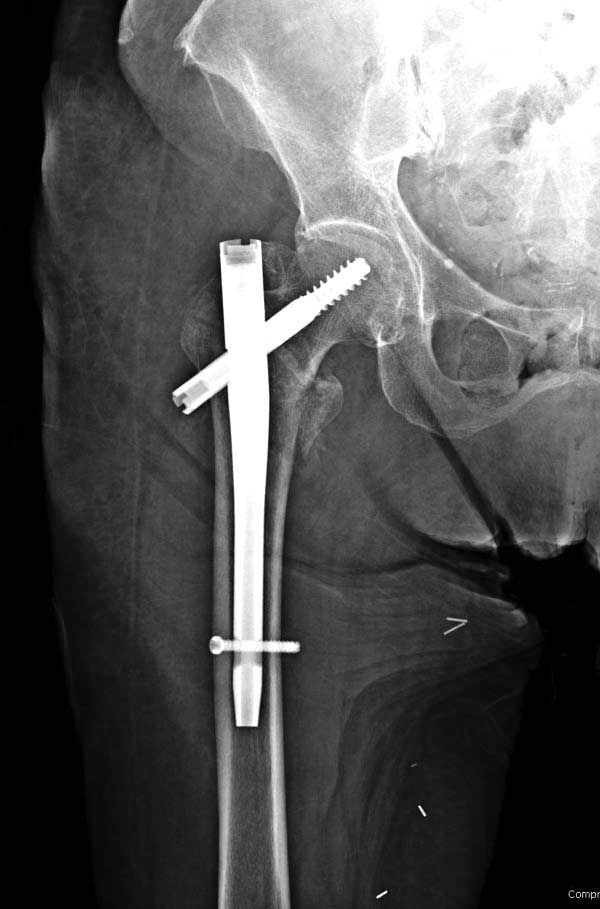

Повторно поступает после двух с половиной лет, где обнаруживается перелом на второй стороне. Немного сложно, но для фиксации выбрали Antegrade InterTan Smith Nephew Nail и с момента фиксации более 3х мес.